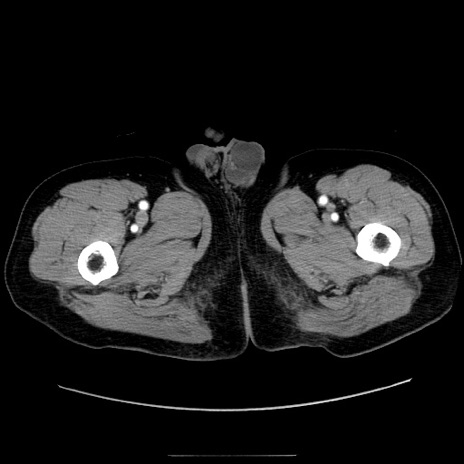

症例30(横断像)

【症例】80歳代男性

【現病歴】約6時間前から臍下部痛が出現。次第に腹部膨隆・背部痛も生じてきたため来院。背部痛の場所は変化しない。

【身体所見】意識清明、BT 36.3℃、BP  131/87mmHg、P 87bpm、SpO2 100%(RA)、臍周囲自発痛・圧痛あり、反跳痛なし、自発痛部位に一致して板状硬あり、腹部膨隆、腸雑音減弱、CVA tenderness両側陰性。